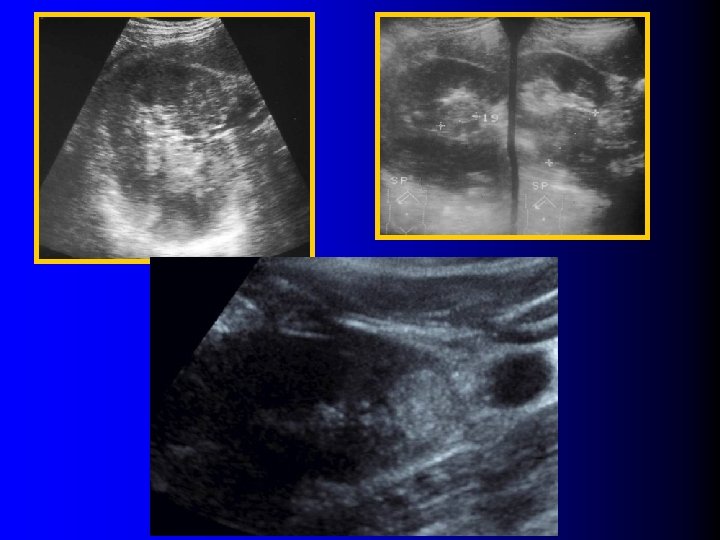

Tumeur hyperéchogène l Indices de malignité – – – l Hyperéchogénicité moins prononcée Anneau périphérique hypo-échogène Caractère très hétérogène ou micro-kystique Calcifications Croissance rapide ? Indices de bénignité – Homogénéité – Caractère atténuant Siegel CL et al, Radiology 1996; 198: 789 Halpenny D et al Clin Radiol 2010; 65: 99

Tumeur hyperéchogène l Indices de malignité – – – l Hyperéchogénicité moins prononcée Anneau périphérique hypo-échogène Caractère très hétérogène ou micro-kystique Calcifications Croissance rapide ? Indices de bénignité – Homogénéité – Caractère atténuant Siegel CL et al, Radiology 1996; 198: 789 Halpenny D et al Clin Radiol 2010; 65: 99

Echographie l Peu l La contributive…. plupart des AML sans graisse sont hypoéchogènes !!!

Echographie l Peu l La contributive…. plupart des AML sans graisse sont hypoéchogènes !!!